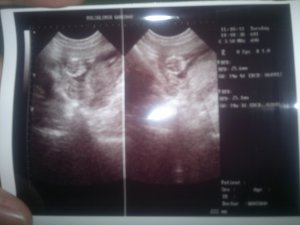

Baby Week 14

Gambar di atas menunjukkan kepala bayi disebabkan baby berpusing-pusing di dalam rahim ketika proses ultrasound (scan)

Video –

Video yang menunjukkan pergerakan baby di mana rahang gigi dan tulang-tulangnya (kaki dan tangan) sudah kelihatan. Baby juga sudah menghisap jarinya sendiri dan tersedu-sedu (Dr. ckp maybe isterinya kurang minum air kot).